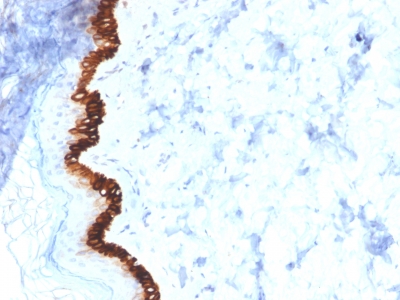

IHC (Immunohistochemisry)

(Formalin-fixed, paraffin-embedded human Basal Cell Carcinoma stained with Cytokeratin 15 Mouse Monoclonal Antibody (KRT15/2554).)